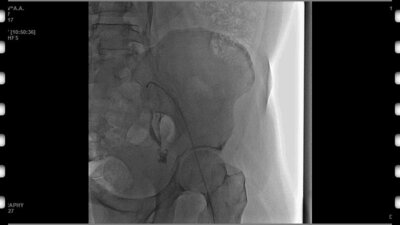

Стенты в урологии